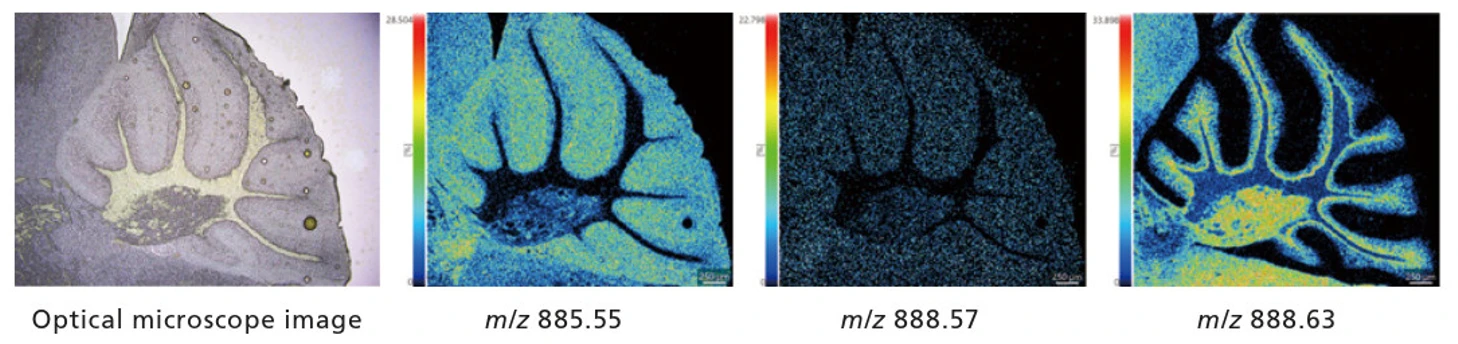

Spojení pozorování z optického mikroskopu se snímky z MS.

MS snímky lze získat flexibilně a porovnat je s pozorovacími snímky, buď celou oblast obrazu, nebo její detailní části.

Výsledky měření mozečku s prostorovým rozlišením 5 μm:

- Vzorek: Celý mozek myši

- Matrice: 9-AA

- Oblast měření: 662×595(393 890 pix)

- Doba měření: přibližně 2,2 hodiny

Oblast v červeném rámečku níže (mozeček) byla měřena s rozlišením 5 μm.